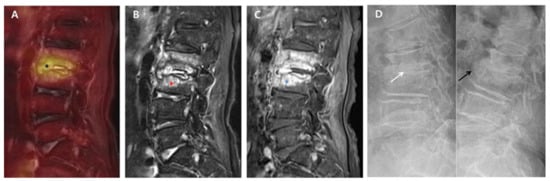

Figure 1. 18F-FDG-PET/MRI immediately after successful antibiotic therapy and radiographs at six-month follow-up in a patient with autofusion (group A). A 78-year-old female patient shows PVO of L2–3 on 18F-FDG-PET/MRI with SUVmax 5.03 of the intervertebral structure (black asterisk) after 56 days of ceftriaxone (ESR 71 mm/h and CRP 0.67 mg/dL). In the distribution pattern of the PVO lesion, 18F-FDG uptake (black asterisk) on 18F-FDG-PET (A) is limited on the damaged disc and endplates (grade II). However, T2FS MRI (B) and T1C MRI (C) show significantly increased high signal intensity (red asterisk) and contrast enhancement (blue asterisk) on the overall PVO lesion (grade III), respectively. On the dynamic radiographs at six-month follow-up (D), stable intervertebral structure presenting with the formation of syndesmophyte (black arrow) is noted with no intervertebral gap (white arrow). 18. F-FDG-PET/MRI, 18F-fluorodeoxyglucose positron emission tomography/magnetic resonance imaging; SUVmax, maximum standardized 18F-FDG uptake value; PVO, pyogenic vertebral osteomyelitis; CRP, C-reactive protein (normal range of < 0.5 mg/dL); ESR, erythrocyte sedimentation rate (normal range of <25 mm/h); T2FS, T2-weighted fat saturation; T1C, T1-weighted contrast; MRI, magnetic resonance imaging.